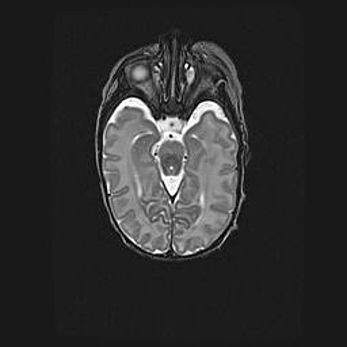

Сообщающаяся гидроцефалия. Кистозная энцефаломаляция головного мозга.

Возраст: 3 месяца 4 дня

Вес: 3100 г

Пол: женский

Окружность головы: 34 см

Срок гестации: 31 неделя

Кистозная энцефаломаляция головного мозга - одна из форм поражения головного мозга в детском возрасте. Характеризуется возникновением множественных и распространённых кист в коре, белом веществе и подкорковых образованиях головного мозга у плодов, новорождённых и детей раннего возраста. Развитие кистозной энцефаломаляции связано с внутриутробной асфиксией и гипотонией, родовой травмой, тромбозом синусов, пороками развития сосудов, инфекциями, сепсисом и другими причинами. Наиболее значимые инфекционные агенты: вирусы простого герпеса, цитомегалии, краснухи, токсоплазмы, энтеробактерии, золотистый стафилококк и другие.